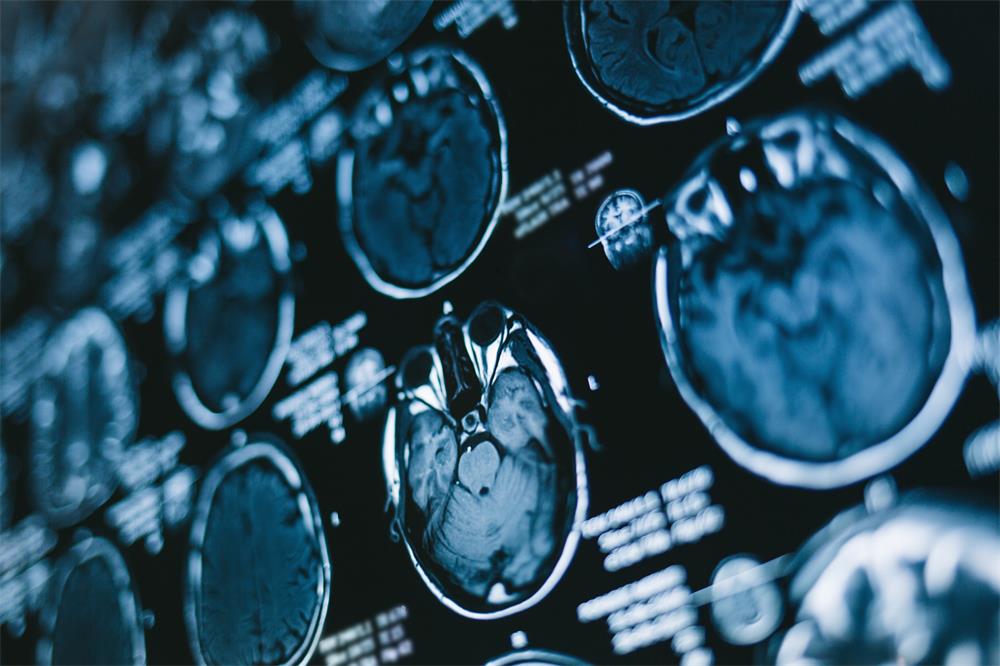

什么是颅内肿瘤?颅内肿瘤是指颅内占位性新生物,分为原发性和继发性两类,起源于脑组织、脑血管、脑垂体、松果体、脑神经和脑膜等组织肿瘤称为原发性颅内肿瘤。

INC国际神经外科医生集团提示,头痛是颅内肿瘤的主要症状之一。引起头痛是由于脑肿瘤占位效应引起颅内压增高和压迫刺激的结果。脑肿瘤相关表现有头晕、恶心、呕吐、视物模糊、肢体无力、走路不稳、内分泌紊乱等,均需要提起重视。脑肿瘤的治疗多数需要手术,手术愈早愈好。因此,头痛以及相关症状患者,要尽量早来医院排除脑肿瘤可能,早确诊,早治疗。